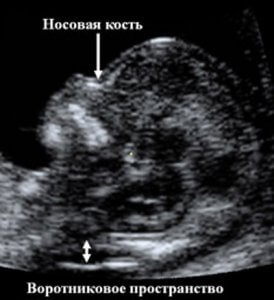

Воротниковое пространство – это скопление жидкости в области шеи у плода

Пока плод еще маленький, он имеет особенности развития, такие, как скопление жидкости в области шеи. По мере развития, начиная со 2 триместра, эта особенность исчезает. Это пространство между оболочками (непосредственно кожа и мягкие ткани шейного отдела позвоночника) и называется толщиной воротникового пространства. Этот показатель учитывается при скрининге первого триместра, который проводится на 11-12 неделе беременности.

Толщина воротникового пространства является важным показателем многих патологий плода, связанных с внутриутробным развитием и хромосомными аномалиями. Проводить подобное исследование целесообразно только с 10 по 14 неделю. До 10-ой недели плод еще слишком маленький и рассмотреть все тонкости с помощью ультразвукового обследования трудно.

Норма толщины воротникового пространства в норме составляет от 0,7 до 2,7 мм в зависимости от того, на какой неделе беременности проводится скрининг. Максимального размера воротниковое пространство достигает на 14-ой неделе, а затем начинает уменьшаться.